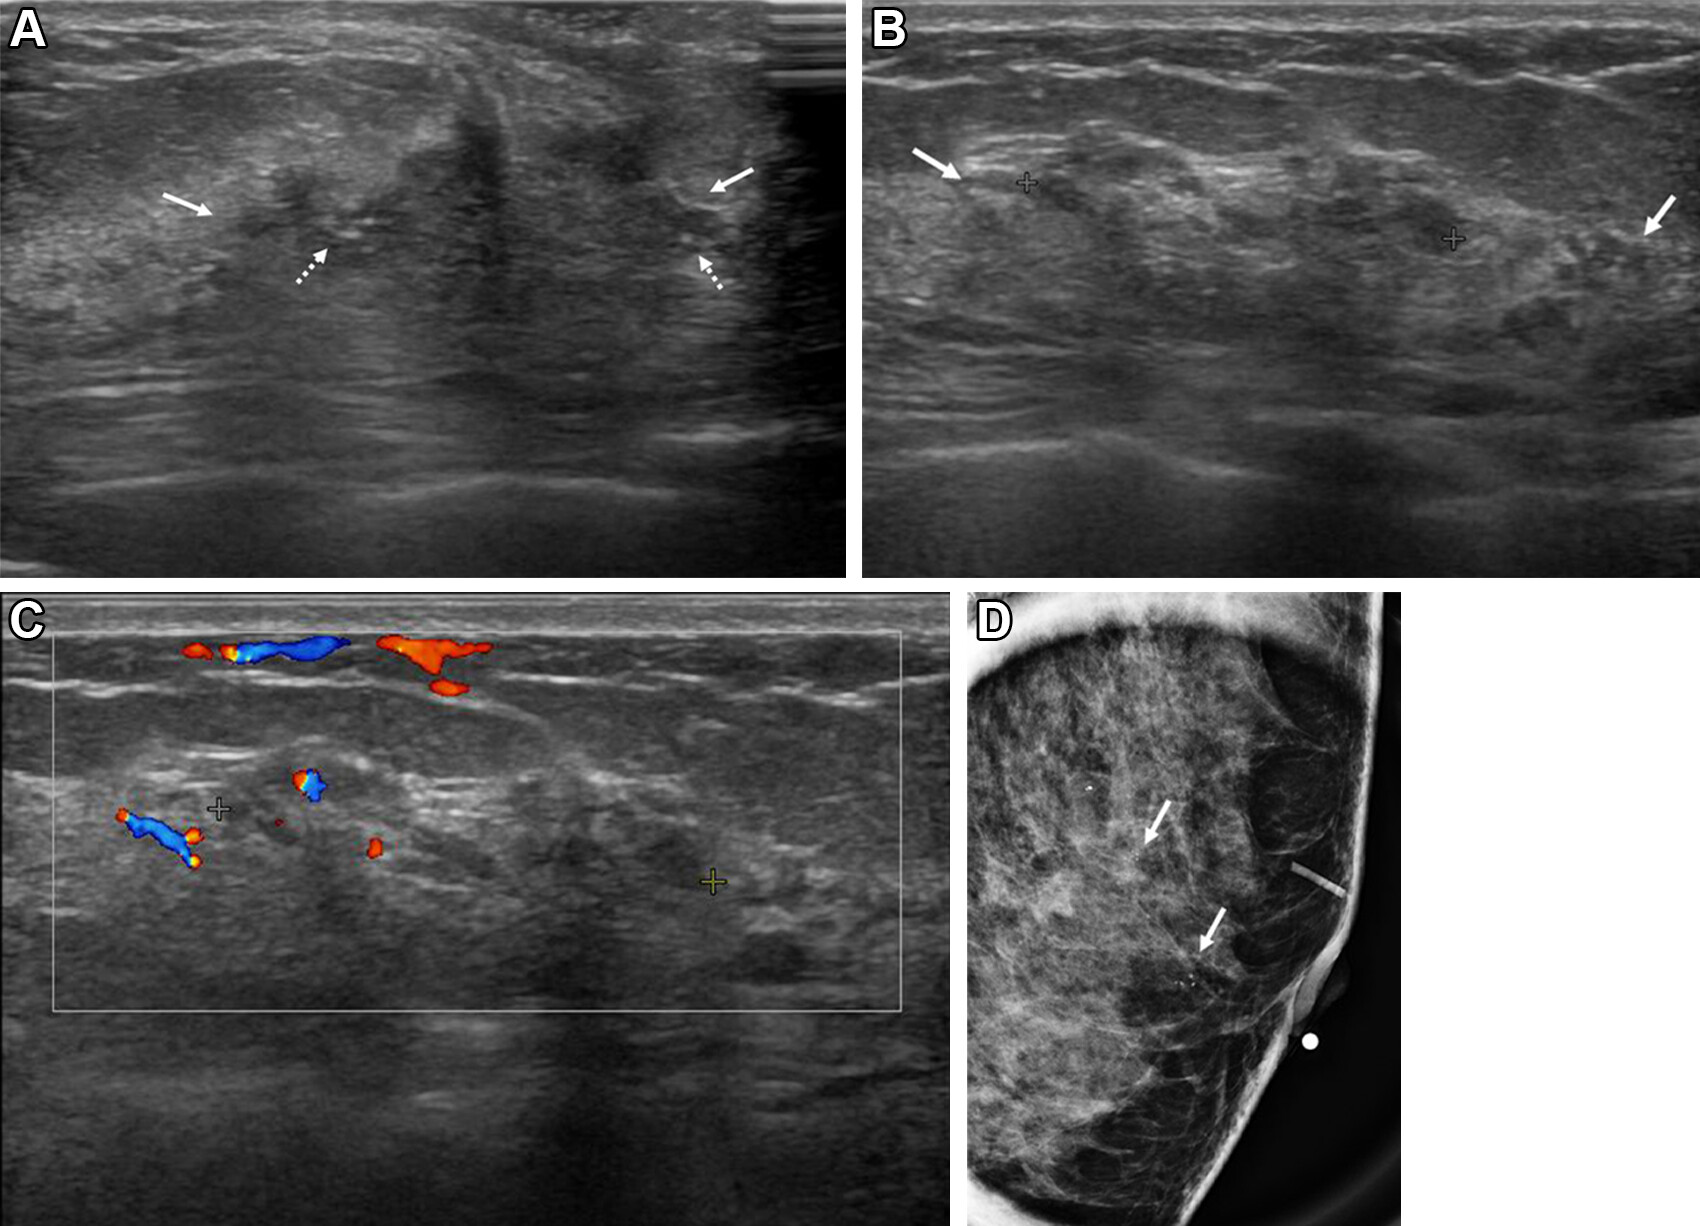

Researchers led by Anwar Rjoop, MD, from the Jordan University of Science and Technology in Irbin, Jordan, found that the presence of an oval-shaped mass and posterior shadowing are significant imaging markers for assessing benign breast lesions categorized as BI-RADS 4c or 5.

Compared with imaging findings in the control group, the presence of an oval-shaped mass was significantly more common in women with benign pathology (p = 0.035). However, the presence of posterior shadowing was significantly less common (p = 0.05) in benign lesions. The researchers observed no significant differences in other imaging characteristics.